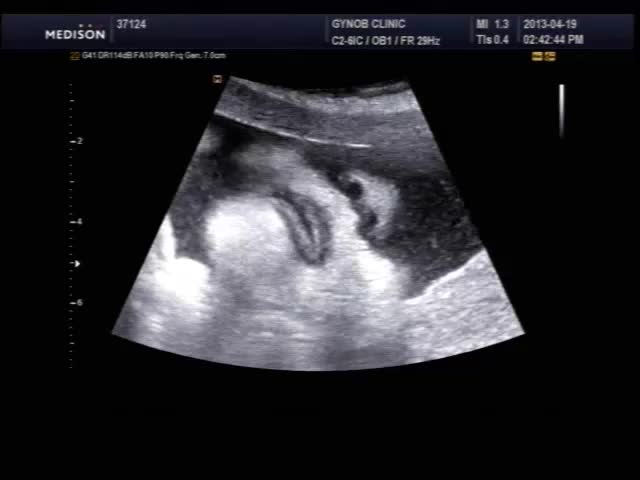

오늘 초음파 보신 산모의 영상인데 태아의 입과 인중 부분이 잘 보이는 편이라 여러분들께 보여드릴 겸, 그리고 설명 드릴 것도 있고 해서 올려 봅니다.

초음파 검사시 태아의 입과 인중을 살펴보는 것은 구순열과 같은 기형이 있는가 보는 목적이며 요즘은 초음파 장비 기술이 발달하여 비교적 쉽게 중기에 진단이 가능합니다.

태아는 뱃속에서도 보고 듣고 먹고 다 할 수 있는데 위 영상을 보시면 태아가 입을 오물거리면서 무언가를 말하는 것도 같지만 사실 말을 하는 것은 아니고 음식을 먹는 운동을 하면서 실제 양수를 삼키는 모습입니다.

mouth.mp4.jpg (19.94 KB, 다운수: 444)

mouth.mp4.jpg

몇주나 되면 저렇게 뚜렷한 얼굴 형태가 보이나요..??!!!

뻐끔거리는 입도 잘 보이고 콧구멍도 잘보이고~~ 완전 신기하네요~~!! ^0^

24주 이상되면 다 저런 모습으로 볼 수 있습니다. 물론 아기 자세가 받쳐주어야 하지만....  등록시간 2013-04-19 19:01